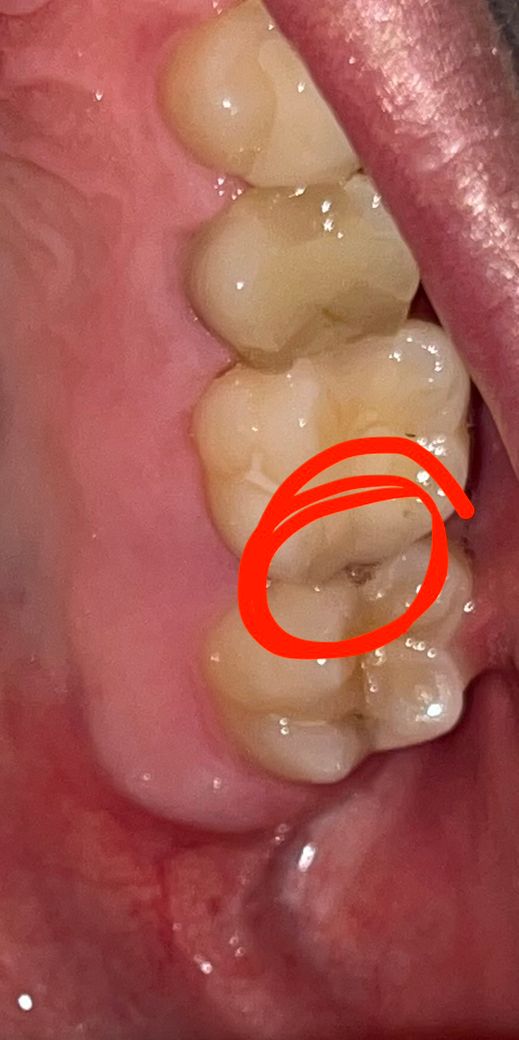

어금니에 구멍이난거같아요 음식물이 자주 낍니다

2달정도 됐는데 평소에 안아프고 밥먹을때 음식물이 자주 끼고요 혀로 느껴봤을때 살짝 뚫려있는 느낌이 들어요 충치인가요..?ㅠㅠ 심각한걸까요?

사진으로 보이는 이것은 인접면에 충치가 생긴 것으로 보입니다. 충치가 생기게 되고 빈 공간이 생기게 되어 해당 부위에 이물질이 계속 들어가게 됨으로써 충치가 더 진행된 것으로 보입니다. 우선 충치를 제거해야 하며 충치를 제거했을 경우 신경까지 충치가 진행되어 있다면 신경 치료가 필요할 수 있습니다.

치아 사이에 충치가 생겨서 구멍이 생긴거 같습니다. 치과에 가셔서 엑스레이를 찍어보시고 치료를 받으시는게 좋을것같습니다.

네 인접면 충치가 맞습니다 음식물이 자주끼어있으면 충치가 더 진행될 겁니다 신경치료 가능성이 있고 일단 인레이를 시도해봅니다